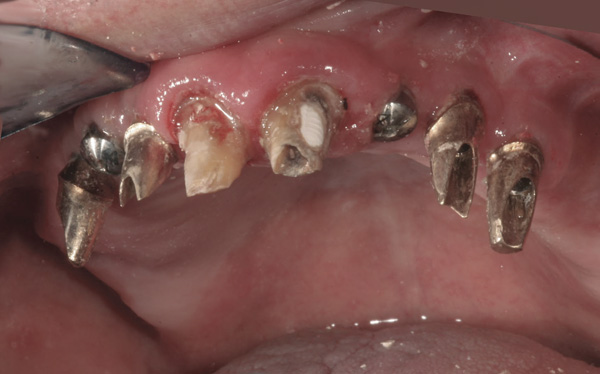

Results: A decision was made to re-prepare all of the abutments intraorally (Figure 3) so that all abutment margins would be at or below the gingival margin. (Of note, tooth Nos. 8 and 9, also shown in Figure 3, were later submerged for the case to be fully implant-supported.) While re-preparation greatly improved the esthetics of the final result, it required retraction cord placement, new impressions, and new castings.

(Note: A separate but similar type of case shown in Figure 4 and Figure 5 further illustrates intraoral abutment re-preparation.)

Figure 3 Abutments re-prepared intraorally.

Figure 3

Figure 4 Following osseointegration of an implant at No. 12, recession was observed at the fixture-level impression stage of No. 13; it was decided to re-prepare the margins of the CAD/CAM custom abutment of implant No. 12. Retraction cord was placed prior to preparation to avoid tissue injury and improve visibility of both tooth No. 11 and the implant custom abutment margin. As expected, recession was greater along the distal side of abutment No. 12, adjacent to the healed extraction/newer implant site.

Figure 4